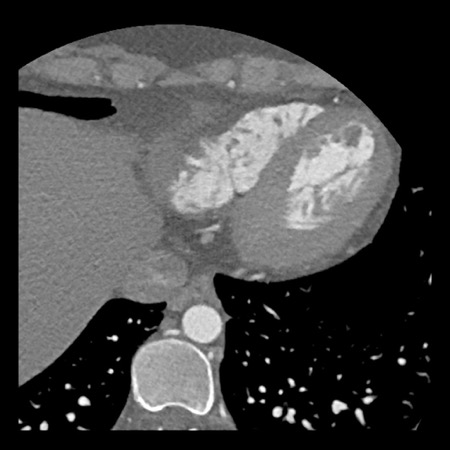

Continue with the next images of the same patient…

Same patient.

Double-oblique (A) and volume-rendered (B) images of the LAD showing the

location and the length of the plaque.

Also, the stenosis in the D2 branch of the LAD can be appreciated on the volume

rendered reconstruction.

Due to the degree of stenosis and the presence of napkin-ring sign (visible on

axial images) this patient underwent ICA where the presence of severe stenosis

was confirmed.